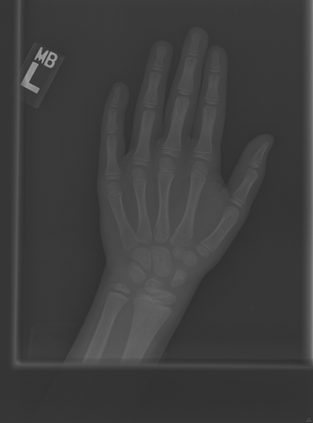

Deep neural networks are increasingly being used for the analysis of medical images. However, most works neglect the uncertainty in the model's prediction. We propose an uncertainty-aware deep kernel learning model which permits the estimation of the uncertainty in the prediction by a pipeline of a Convolutional Neural Network and a sparse Gaussian Process. Furthermore, we adapt different pre-training methods to investigate their impacts on the proposed model. We apply our approach to Bone Age Prediction and Lesion Localization. In most cases, the proposed model shows better performance compared to common architectures. More importantly, our model expresses systematically higher confidence in more accurate predictions and less confidence in less accurate ones. Our model can also be used to detect challenging and controversial test samples. Compared to related methods such as Monte-Carlo Dropout, our approach derives the uncertainty information in a purely analytical fashion and is thus computationally more efficient.